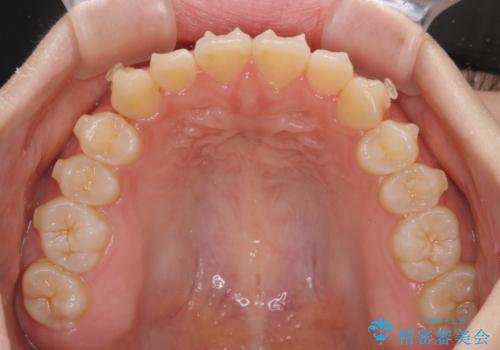

前歯のデコボコを整える インビザラインによる矯正治療

- 上下前歯のデコボコを気にして来院された患者様です。

叢生は軽度であり、ワイヤー矯正でもマウスピース矯正でも対応可能であったので、好きな装置を選んでもらいました。

毎日の装着時間をしっかりと守っていただいたことで、1年程度で無事に治療を終えることができました。